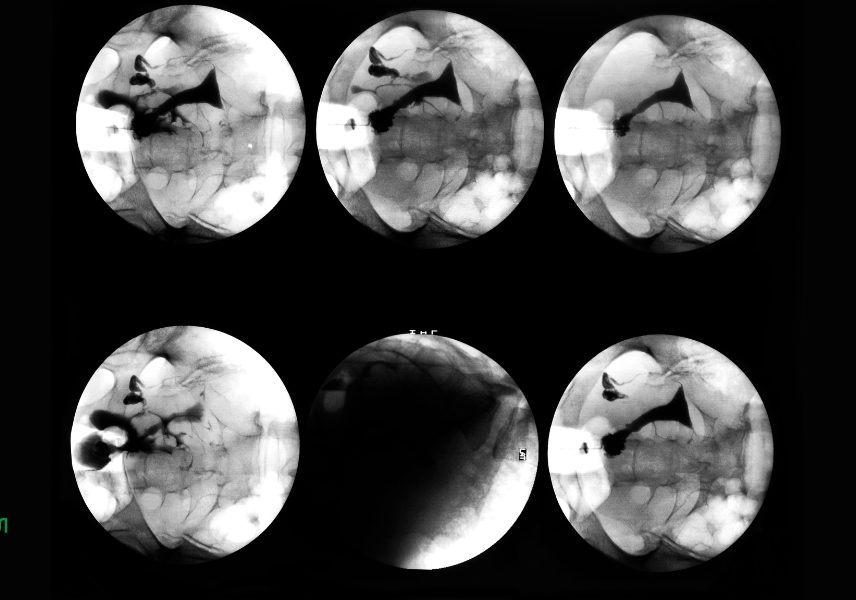

Диагностицирането на вътрешно кървене обикновено изисква медицински тестове, физически преглед и проверка на предходни заболявания. За наранявания може да е необходим образен тест. При нужда се прави рентгенова снимка, която показва състоянието на костите.

Компютърната томография е безболезнен метод, при него чрез специален рентгенов апарат, се осигурява достъп до различни органи и структури, които не могат да бъдат визуализирани по традиционни начини.

Ангиографията е образен тест, който изследва отделни кръвоносни съдове, показва състоянието на аортата и нейните разклонения. Изобразява пространството на артерии, вени, сърдечни кухини.